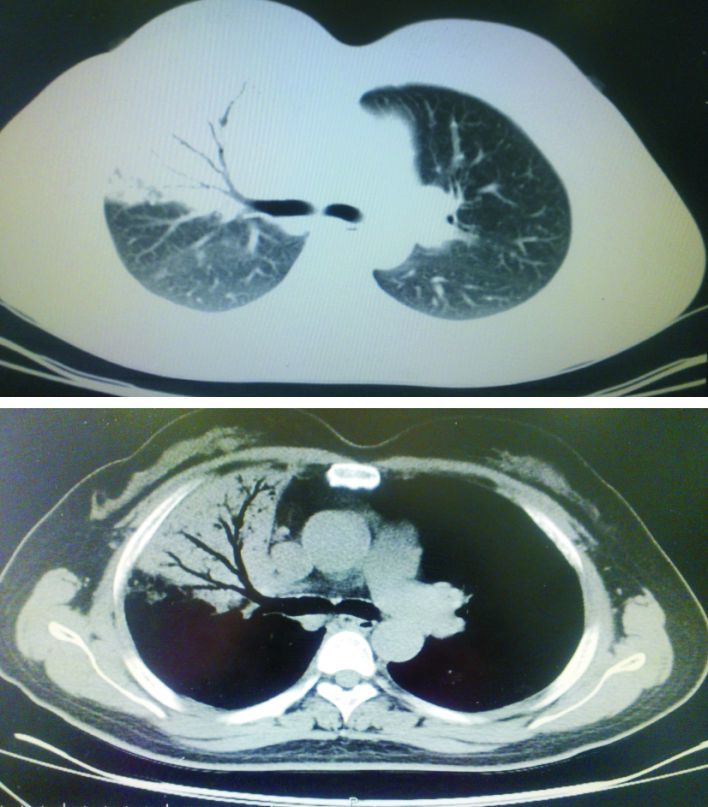

圖2

2010年4月病例2胸部CT示右肺中葉實變影,其內可見支氣管氣相

病例2?患者女性,50歲。于2010年4月23日因“咳嗽、活動后氣短、間斷低熱9年余,加重10 d” 入院。9年前患者受涼后出現發熱,最高體溫達38.0 ℃,伴有咳嗽、胸痛、盜汗,于我院就診。胸部CT示右肺中葉內側段見大片狀高密度影,其內見支氣管氣相,左肺上舌段見小片狀模糊影,縱隔淋巴結不大(圖 2)。纖支鏡示右中葉內側段支氣管口黏膜充血,有少許膿苔,黏膜略不平。肺泡灌洗及刷片未查到抗酸桿菌及異型細胞。右中葉支氣管黏膜活檢示炎癥改變。診斷為肺炎。給予抗感染治療后,體溫正常、咳嗽減輕、胸痛緩解出院。